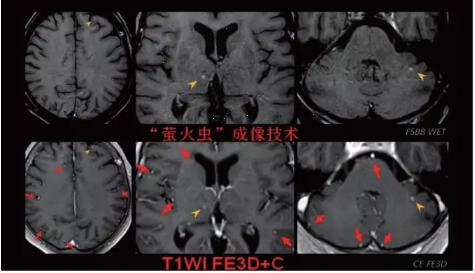

見所未見 微小腫瘤無處遁藏——

“螢火蟲”成像技術 顱內腫瘤微小病灶檢出新發(fā)現(xiàn)

此技術主要用于神經(jīng)系統(tǒng)惡性腫瘤,以及其他腫瘤腦轉移瘤篩查。傳統(tǒng)情況下做腫瘤腦轉移篩查,很容易漏掉5mm以下小病灶,臨床發(fā)現(xiàn)后干預治療比較晚,要實現(xiàn)2mm高空間分辨率和超薄層全腦掃描在保證信噪比的情況下需要很長時間大概十多分鐘,而且薄層增強序列顱內血管呈高亮信號,會干擾顱內小病灶的觀察,血管和小病灶區(qū)分困難。佳能”螢火蟲”成像技術既可以實現(xiàn)高空間分辨率和超薄層(最薄可實現(xiàn)0.2mm)全腦掃描,掃描時間短,2-3分鐘即可實現(xiàn)全腦3D掃描,同時避免了血管高亮信號的干擾,對顱內原發(fā)或繼發(fā)的微小腫瘤檢查有重大意義。“螢火蟲”成像技術具有磁敏感效應,對于亞急性血敏感敏感,可以區(qū)分出血和強化的腫瘤。